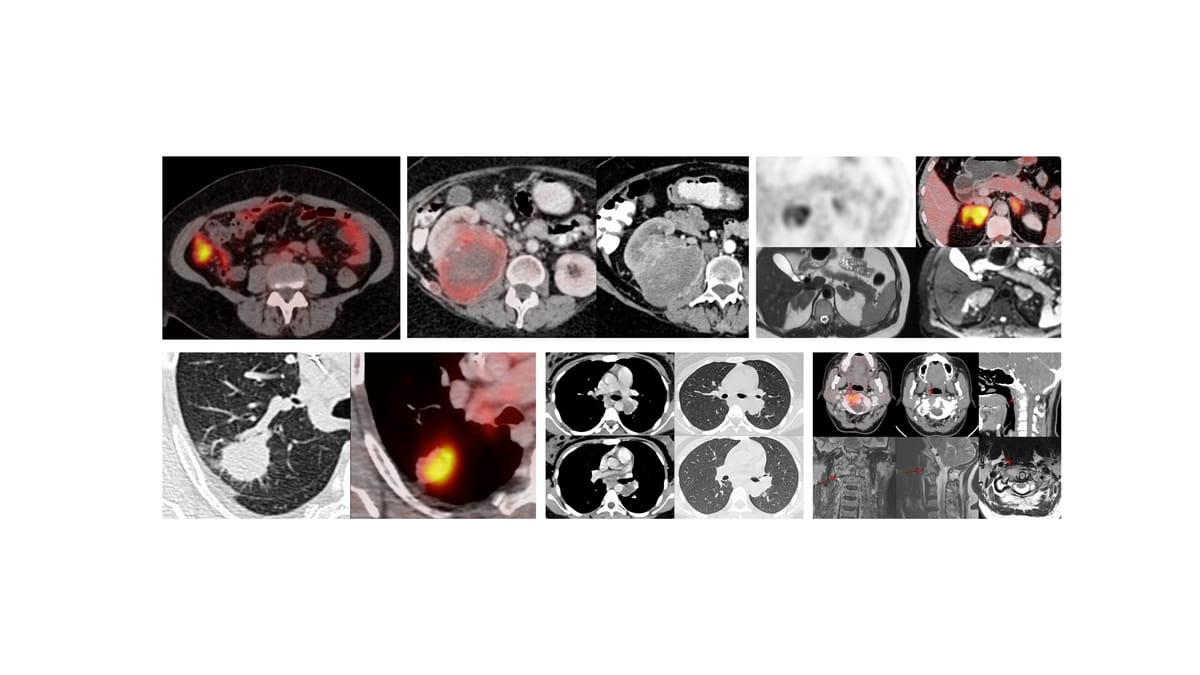

63-years old, CKD on dialysis for 4 years developed bilateral chylothoraces 3 months ago and was referred for a CT lymphangiogram (CTL)

While there are different ways of doing lymphangiograms, a relatively new technique is CTL with intranodal injection of non-ionic iodinated contrast and rapid scanning within 2-5 minutes.

The video explains what I did - injecting a retroperitoneal node in the prone position instead of an inguinal node with a successful CTL showing lymphatic duct obstruction at the D5-6 level.

The paradigm has changed. This procedure is now simple and can be performed by anyone who can put a needle into a node proximal to the site of obstruction with intranodal injectino of regular non-ionic iodinated contrast.